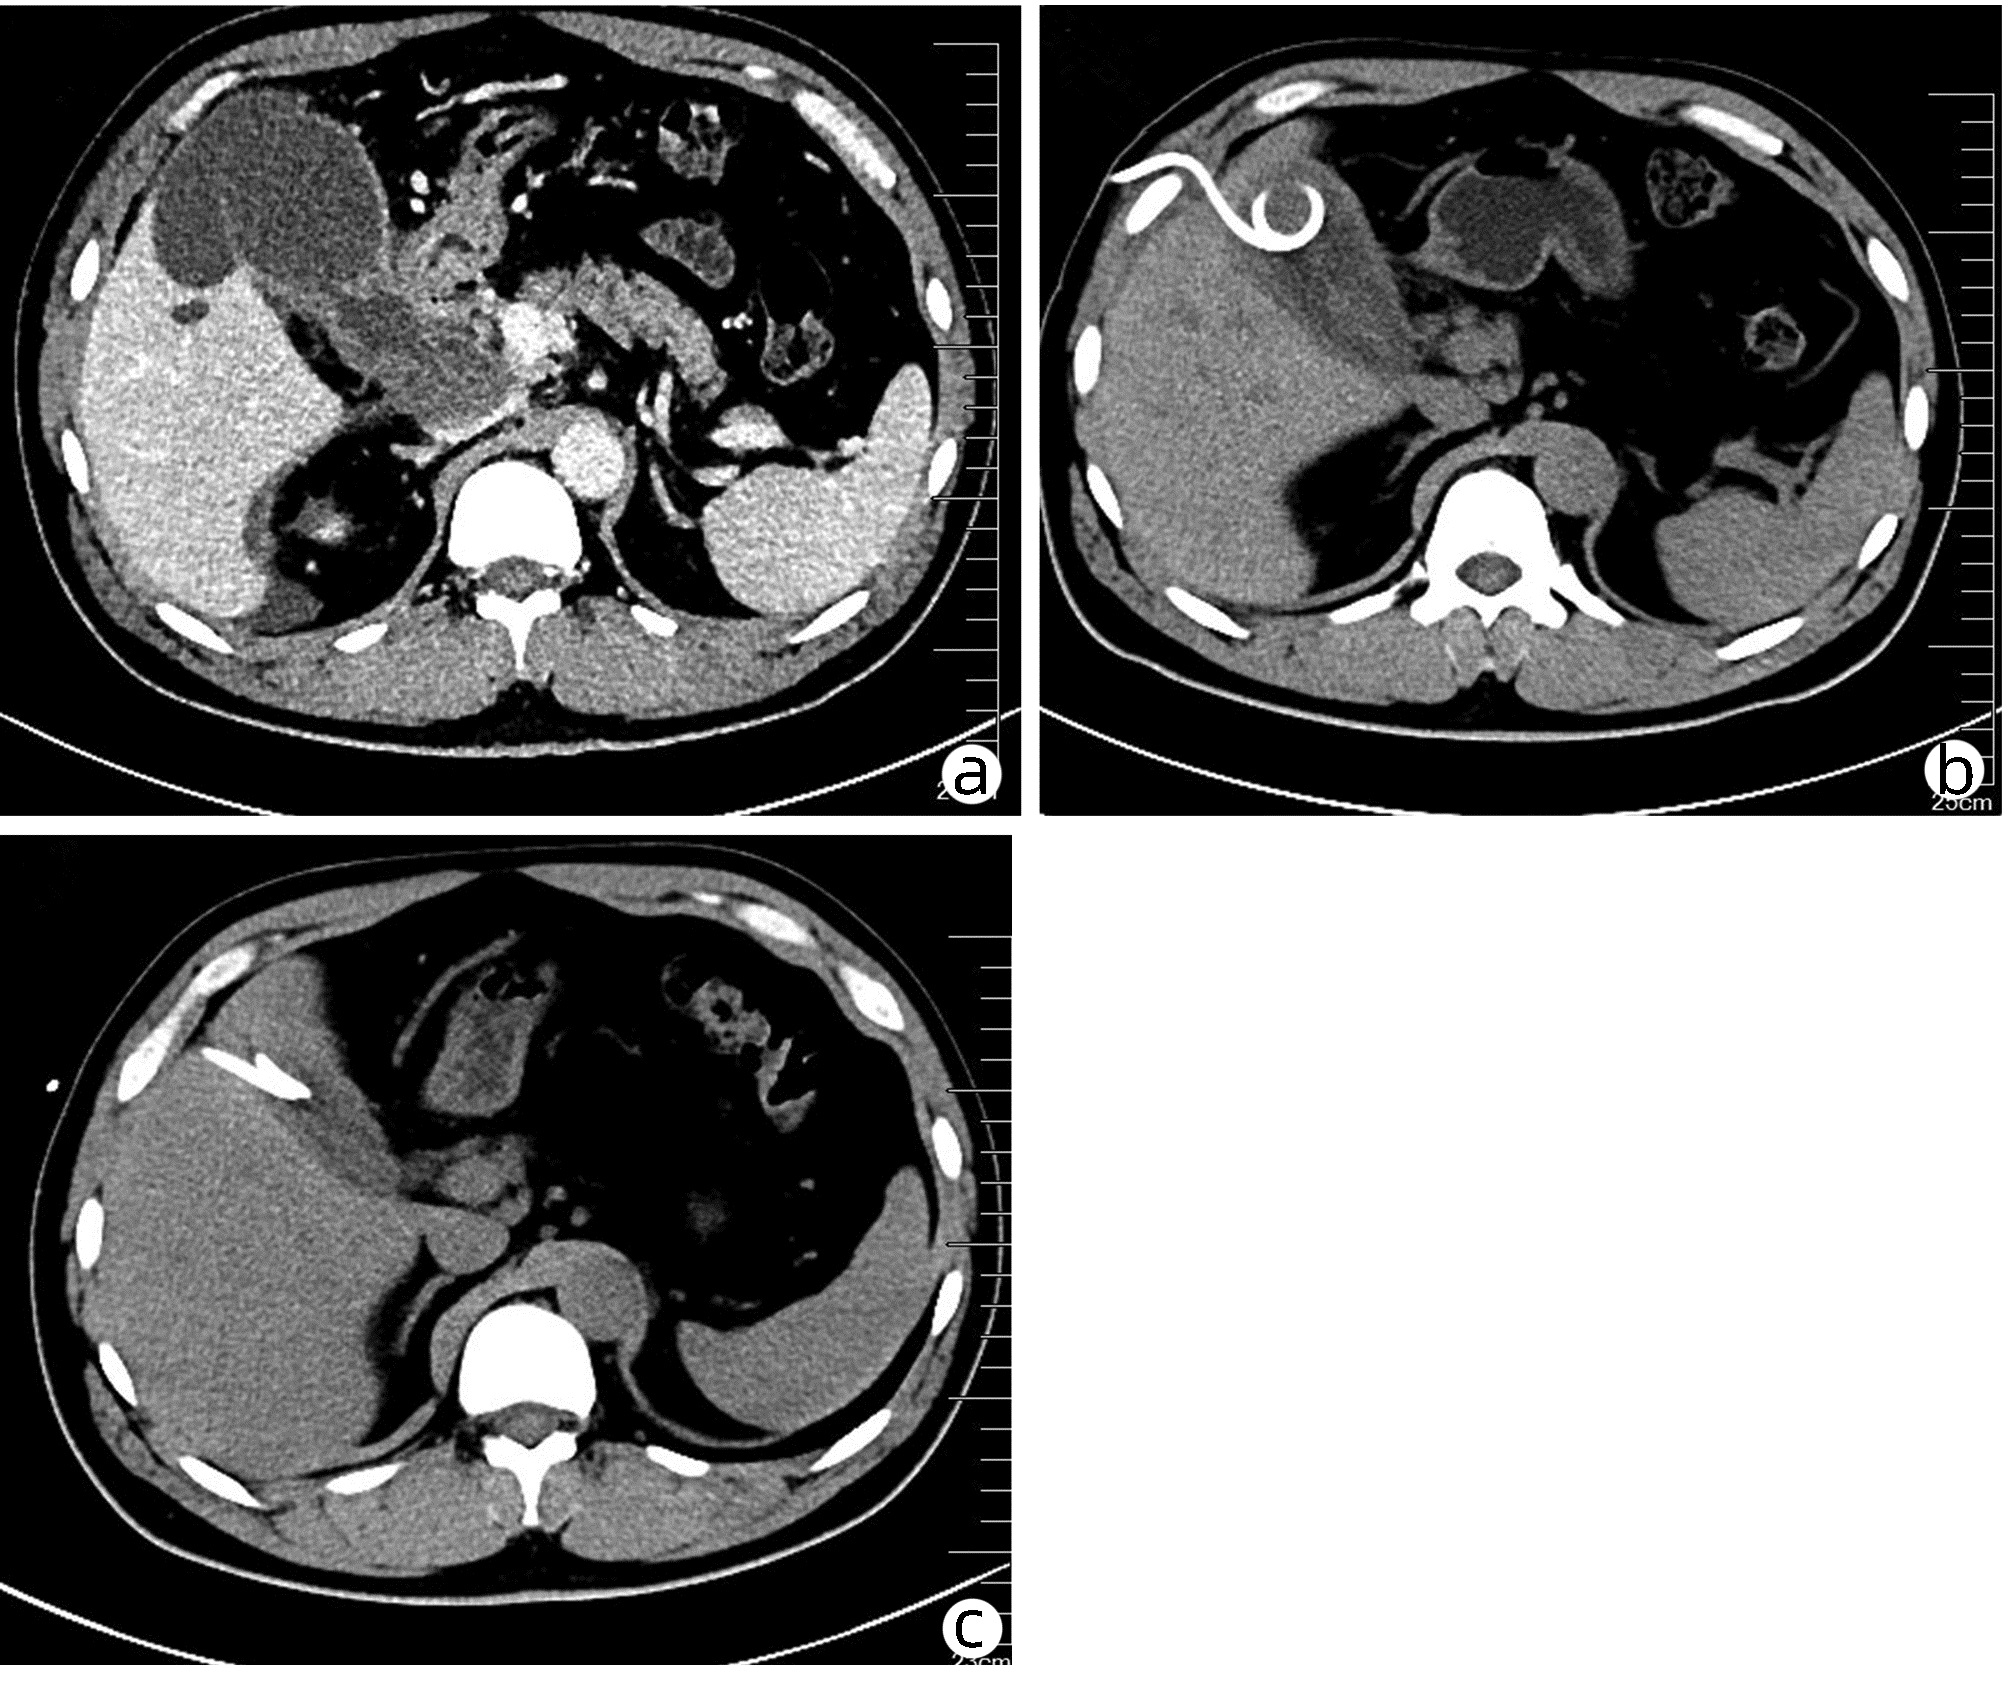

局部栓塞联合靶向免疫综合治疗肝肉瘤样癌1例报告

雷进, 张林枝, 陆荫英, 陈博文, 左石

2022, 38(4): 880-882. DOI: 10.3969/j.issn.1001-5256.2022.04.026

摘要(1323) HTML (453) PDF (3487KB)(82)

摘要: